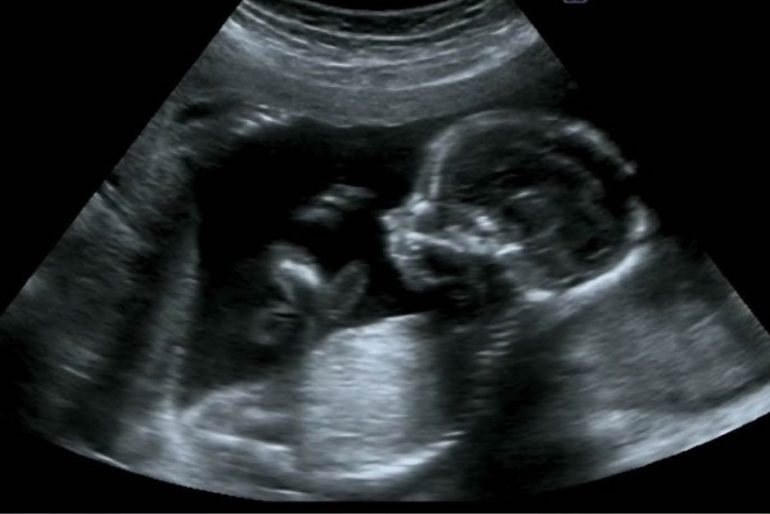

ورم ليفى جنين داخل الرحم اثناء الحمل

تصاب النساء بصدمة كبيرة عند اكتشاف وجود ورم ليفى فى الرحم أثناء الحمل لأنها تشعر بالقلق على مستقبل طفلها وصحته.

وأضاف "مصطفى" فى بعض الحالات يمكن إستئصال الورم الليفى أثناء الولادة القيصرية لكن هناك خطورة لأن فرصة حدوث نزيف رحمي كبيرة أثناء الجراحة بسبب تضخم الرحم وزيادة تدفق الدم أثناء الحمل ويحتاج لفترة لتعود للمعدلات الطبيعية بعد الولادة، ومن الأفضل عمل فحص بالموجات الصوتية لمتابعة نمو الورم ووضعه لمعرفة إمكانية حدوث أى مشاكل فيما بعد أو تأثيره علي وضع الجنين.